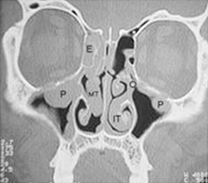

| Orrpolip CT kép. |

A melléküregek állapotáról CT (Computer Tomográfiás röntgen) felvételek alapján tájékozódunk, ezeken a felvételeken jól látszanak az arcüreget kitöltő polipok.

A pontos diagnózishoz és a pontos műtéti terv felállításához az orrtükri kép, az endoscopos vizsgálat és a CT felvételek is szükségesek.